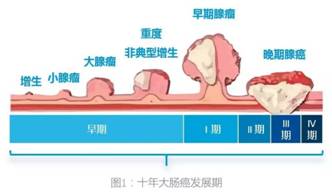

大肠息肉是指发生于大肠黏膜的各种局限性隆起病变,在未确定病理性质前均称为结肠息肉。其发生率随年龄增加而上升。

1、管状腺瘤:一般生长缓慢,分化良好,相对较少发生癌变,癌变率约为1%~5%;

2、绒毛状腺瘤:占腺瘤性息肉的5%~10%,表面呈绒毛状、色略苍白,可有黏液或糜烂,直径多数在2~3cm左右,癌变率约为30%~70%。;

3、管状-绒毛状腺瘤:占腺瘤性息肉的10%左右,管状结构和绒毛状结构所占比例均超过20%,多有粗蒂,大小不一,表面呈结节状或绒毛状,质软。